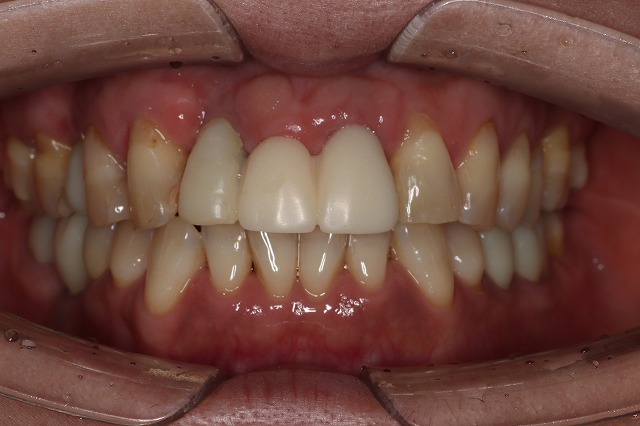

CASE01

Before

After

| 主訴 |

他院で施術の前歯のインプラント治療中最終補綴に納得いかずに来院 |

| 施術内容 |

IM上部構造…4本 / アバットメント…3本 / ジルコニア…下顎6本・上顎3本 / CTG(インプラント)…2部位 / CTG(根面被覆)…1部位 / FGG…2部位 / ポーセレンインレー…上顎4本 |

| 治療期間 |

1年4ヶ月(40回) |